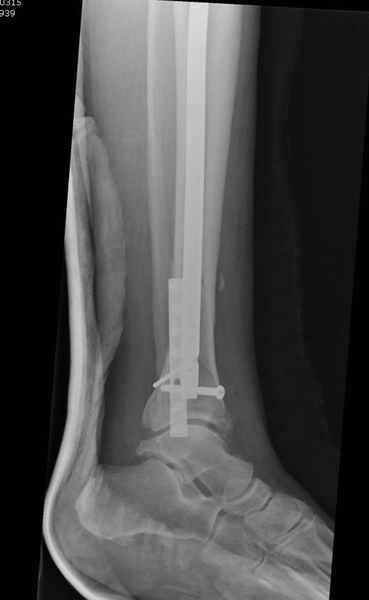

Здесь мы использовали новый Synthes Nail с дополнительными дырками, в проксимальной части 4: по две косых и поперечные (один стандартный а другой динамический), в дистальной части две поперечные, прямая и косая. Вес больного более 120 кг, нагрузку начнем через месяц.

Получилось красиво, поздравляю. Вверху можно было ограничиться одним винтом во фронтальное статическое отверстие, зачем два 45-градусных?

При такий спирали задний край tibia может быть сломан - нет ли этого в данном случае? На всякий случай можно было ввести 1-2 винта 4,5 мм спереди назад мимо гвоздя. Хотя самый дистальный блокирующий винт, возможно, зацепил этот отломок. А какой тут диаметр гвоздя и locking винтов?